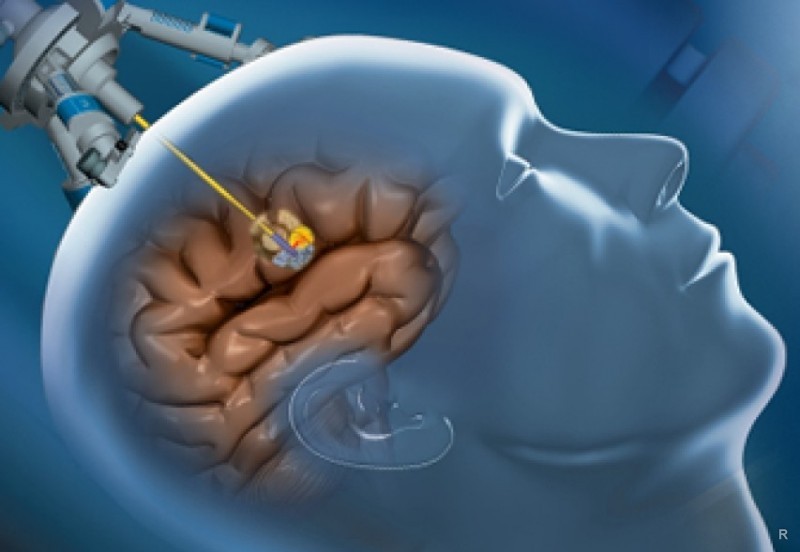

- биопсия опухоли.